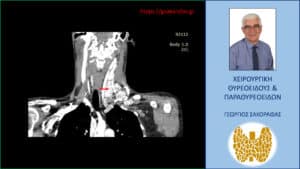

Τα ευρήματα του υπερηχογραφήματος επιβεβαιώθηκαν σε αξονική τομογραφία τραχήλου την οποία προσκομίζει η ασθενής (είχε γίνει πριν το υπερηχογράφημα) (βλ. εικόνες).

Καρκίνος θυρεοειδούς με εκτεταμένη λεμφαδενική διασπορά – Αξονική τομογραφία – απεικόνιση σε κατά μέτωπο διατομή. Απεικονίζεται η εκτεταμένη λεμφαδενική διασπορά στους λεμφαδένες της αριστερής πλάγιας τραχηλικής χώρας. Το κόκκινο βέλος έχει τοποθετηθεί περίπου στο κέντρο της εκτεταμένης λεμφαδενικής διασποράς, που εκτείνεται σε μεγάλη έκταση επί τα εκτός των μεγάλων αγγείων του τραχήλου.

Αξονική τομογραφία – απεικόνιση σε κατά μέτωπο διατομή. Απεικονίζεται η εκτεταμένη λεμφαδενική διασπορά στους λεμφαδένες της αριστερής πλάγιας τραχηλικής χώρας. Το κόκκινο βέλος έχει τοποθετηθεί περίπου στο κέντρο της εκτεταμένης λεμφαδενικής διασποράς, που εκτείνεται σε μεγάλη έκταση επί τα εκτός των μεγάλων αγγείων του τραχήλου.